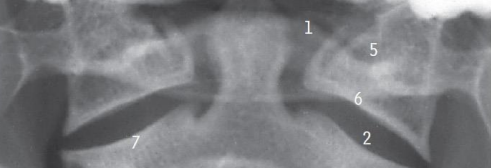

Intraoral view

Arch of altlas.

Atlanto-axial joint.

Body of axis.

Lateral mass of axis

Inferior articular process; Superior articular process

What are the abnormal signs in this radiograph

Alignment (distance between dens and lateral masses of C1 not equal.

Soft tissue swelling -